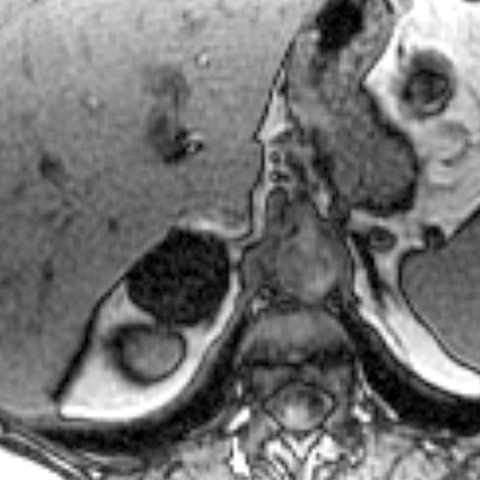

24-year-old-female presents with a 2 year history of an abdominal mass [3 of 3]